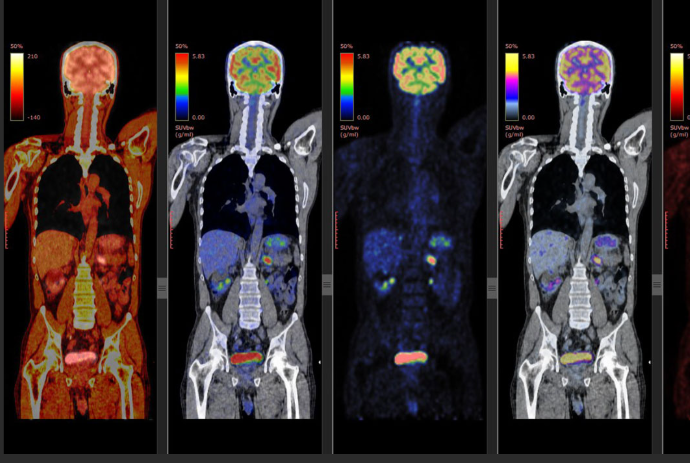

To raise the money needed to get a PET scan.